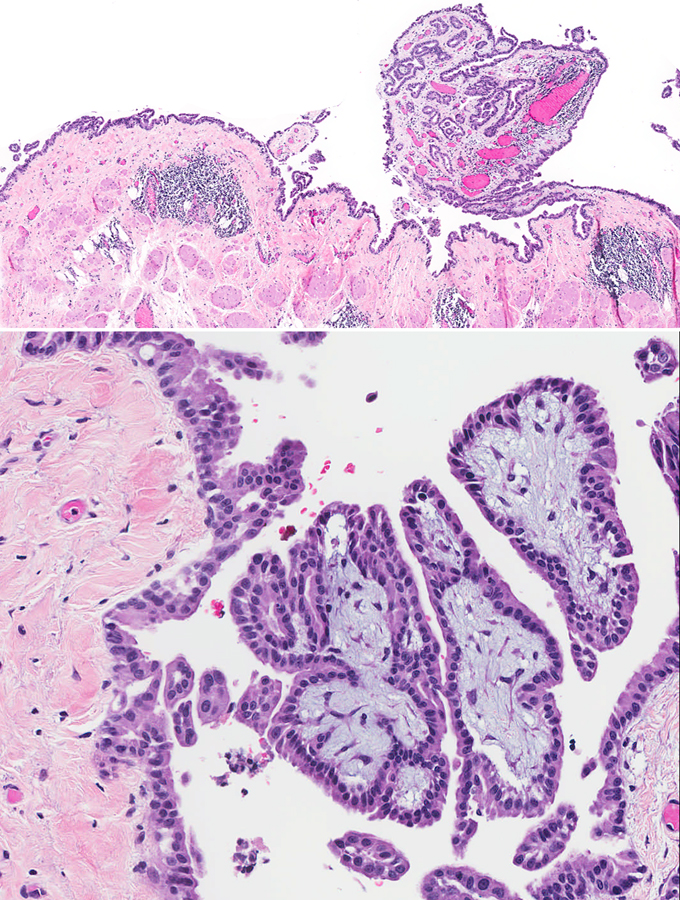

Nivolumab-induced peritonitis with peritoneal mesothelial hyperplasia mimicking metastatic mesothelioma

A 57-year-old man developed a mesothelial proliferation in the peritoneum, several months after he was diagnosed with biopsy-proven epithelioid mesothelioma of the pleura and having undergone several treatments with checkpoint inhibitor immunotherapy. The differential diagnosis was metastatic mesothelioma from the lung primary, versus a reactive process. A diagnosis of atypical mesothelial proliferation was made. Follow-up CT showed no evidence of abdominal disease 5 months later. The complication of serositis following checkpoint inhibitor therapy is reviewed, as well as the differential diagnosis between reactive mesothelial hyperplasia and epithelioid mesothelioma.